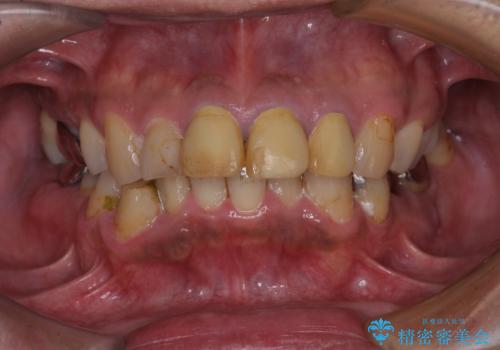

[ 金属アレルギー ] 銀歯を除去するメタルフリー治療

担当医 大元洋佑

![[ 金属アレルギー ] 銀歯を除去するメタルフリー治療の症例 治療前](https://seimitsushinbi.jp/wp/wp-content/uploads/2023/08/e81d14b5b541f23b9fcb9feb23262596-500x350.jpg?v=1692755937)

![[ 金属アレルギー ] 銀歯を除去するメタルフリー治療の症例 治療後](https://seimitsushinbi.jp/wp/wp-content/uploads/2023/08/285add314246a78e4e98332cd6f9956a-500x350.jpg?v=1692755948)